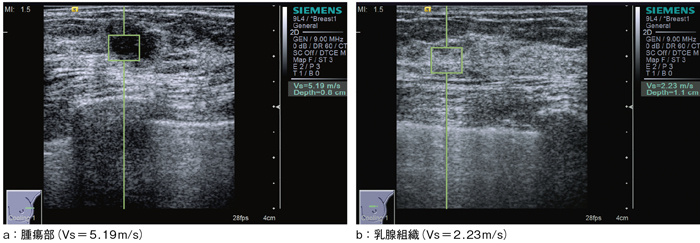

一般に,固体に衝撃を与えると弾性波が発生する。これには縦波と横波があり,それぞれ内部を伝搬する。このうち,横波である剪断弾性波に着目し,その伝搬速度(Vs[m/s])を測ることによって,組織の硬さを定量的に評価するのが,Virtual Touch Tissue Quantification(VTTQ)である。Vsの値が大きいほど,硬い組織であることを意味する。

VTTQでは,剪断弾性波を生体内の測定したい近傍で発生させる手段として,前述のARFIを用いる。収束超音波パルスが照射され,限局的に力の作用を受けた組織には,剪断歪みが生じる。力を取り除くと復元力が働き,組織は振動する。それが剪断弾性波となって,周囲に水平方向に伝搬する。これは,プローブでは感知できない方向であるため,小さなROIの内部を超音波断層法で高速スキャンを行い,組織の微細振動を検出して,剪断弾性波の伝搬速度を求める(図3,4)。

図4 Virtual Touch Tissue Quantificationの例(浸潤性乳管癌)

(画像ご提供:りんくう総合医療センター・位藤俊一先生)